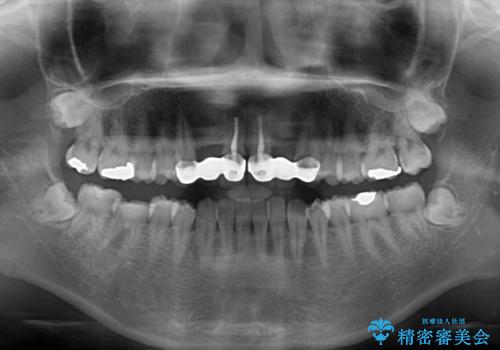

- 審美的ではない上の前歯とデコボコの下の前歯、歯茎が腫れている奥歯を気にして来院された患者様です。

根管治療の必要な歯がいくつかあるため、まずは根管治療を行い、その後インビザラインにて矯正治療を行うこととしました。

矯正治療後に前歯をセラミックブリッジに、奥の銀歯はセラミックインレーやPGAインレー(ゴールドインレー)にて補綴・修復治療を行うこととしました。